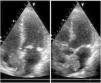

Large biatrial myxoma through an atrial septal defect

Mixoma biauricular gigante a través de comunicación interauricular